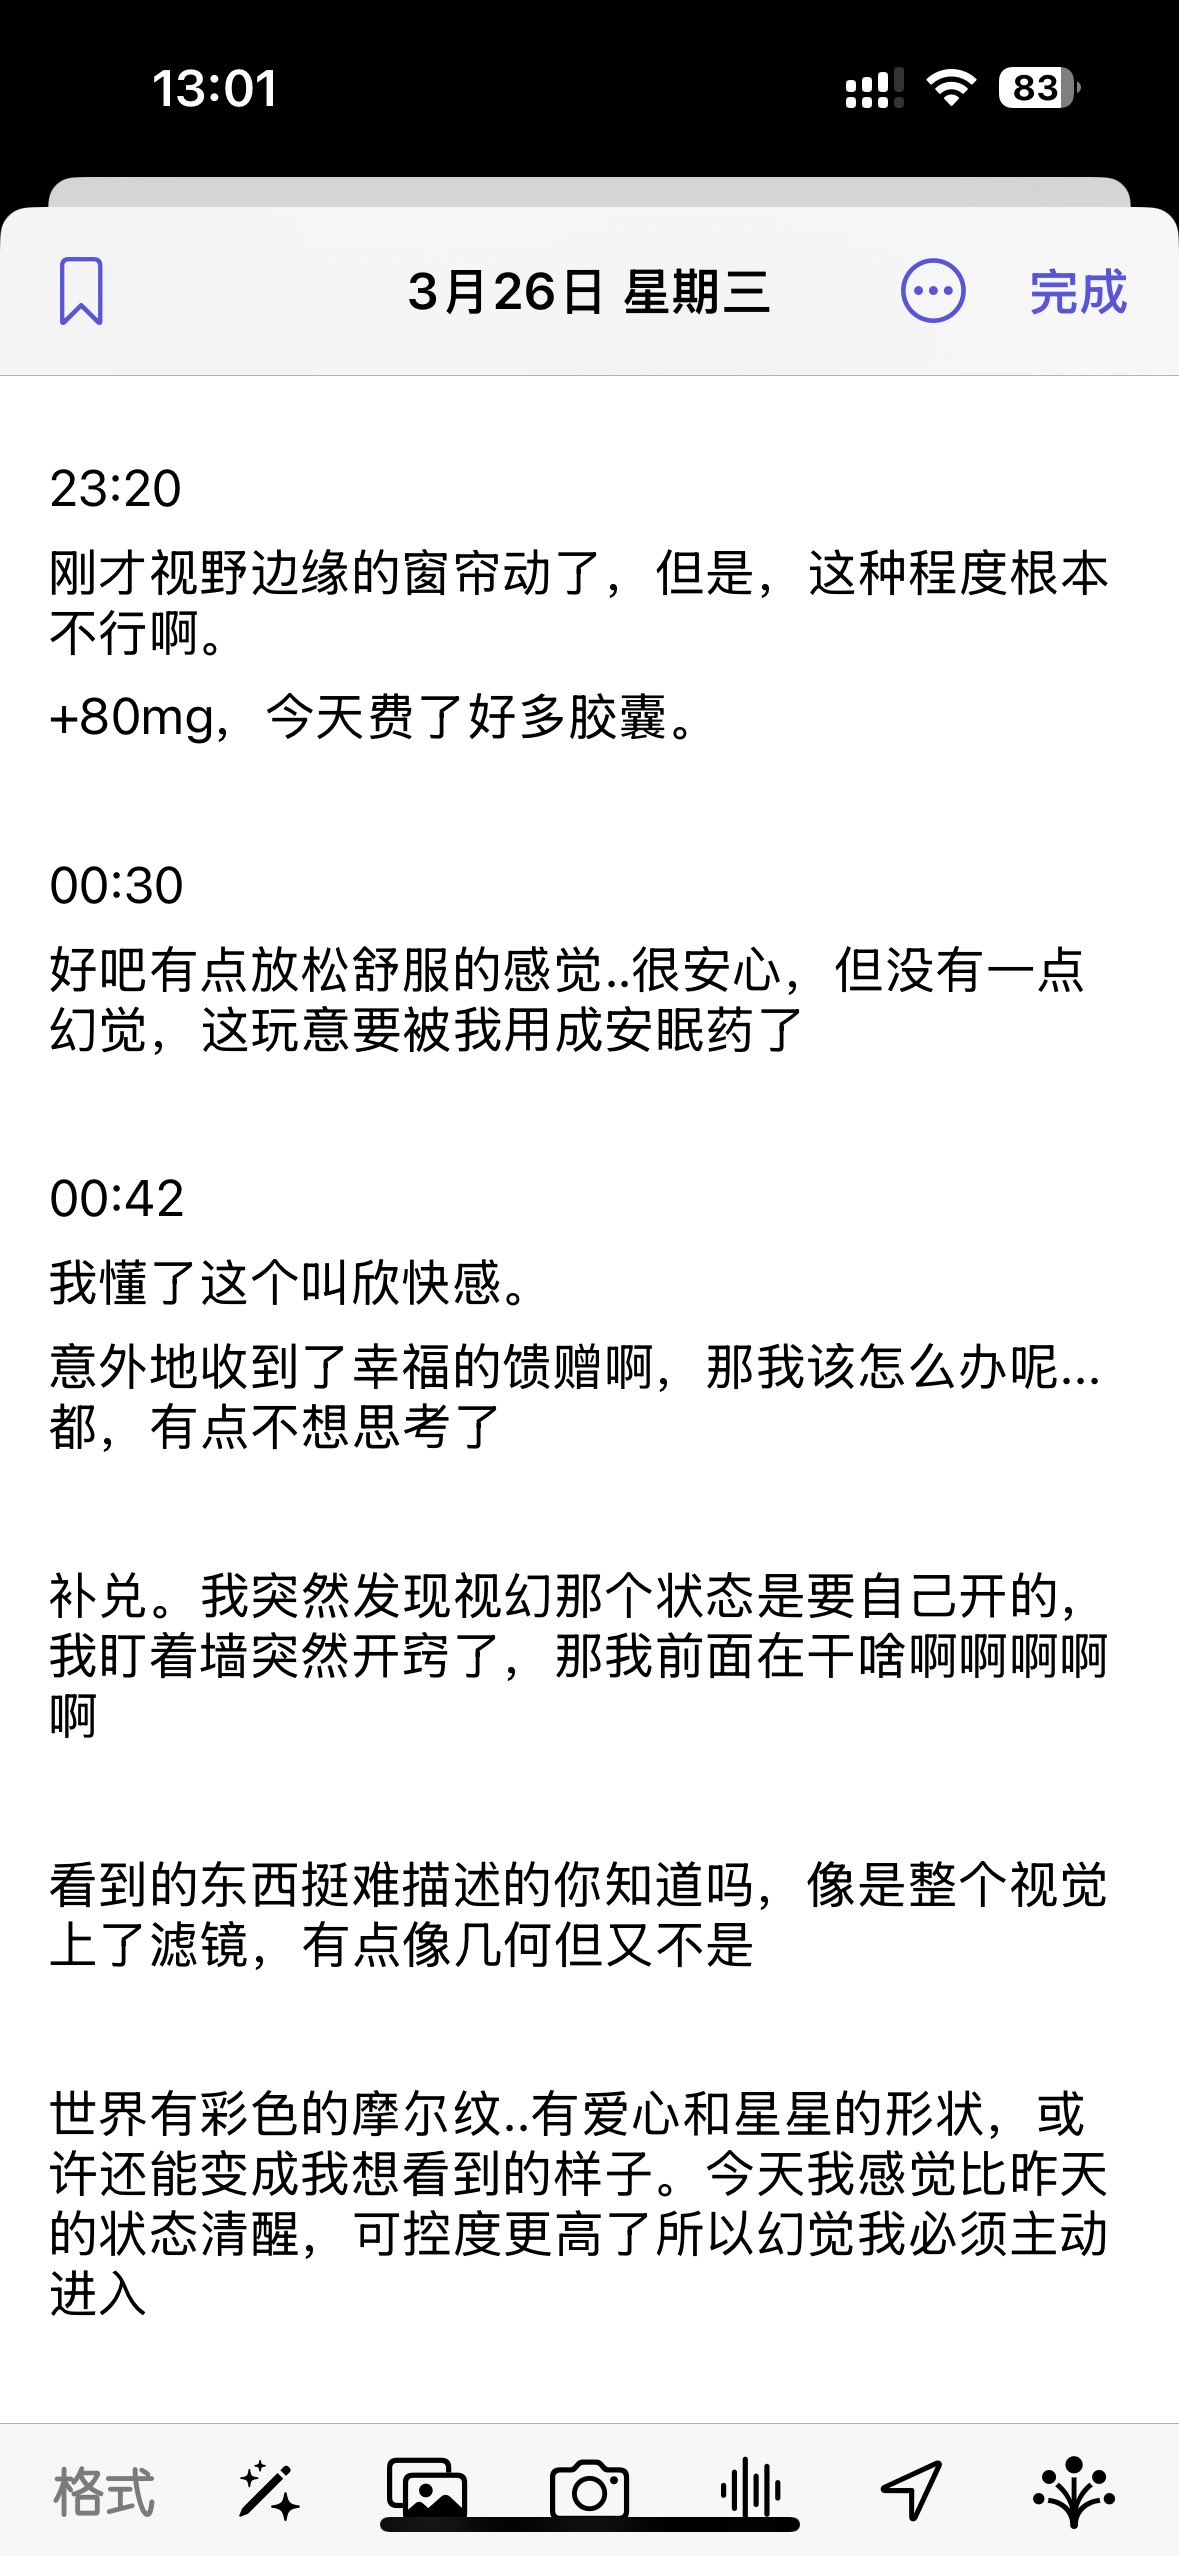

今天起来特别晕,完全不知道是怎么回事,以为是昨天测试物质的副作用我在想这么恐怖,然后怀疑今天是不是丁螺环酮吃了两次,直到我去看用药记录。。

好家伙唑吡坦又骗我吃药了还顺带上了个失忆状态,这下子知道是谁干的了。吃auv之后dxm清除得特别慢...让我感觉要从此告别了的程度,加上我基因检测本来cyp2d6就是中速代谢,这个尾巴就被拖的特别长

想起来昨天是因为完全看不懂字了什么都干不了才睡觉的,还好没去骚扰别人()

炽烈已极 @AnIncandescence醒了躺在床上的时候想着怎么还有内幻呢,像是在拉摇杆操纵游戏里的小人,以一个俯瞰的视角(经典)

炽烈已极 @AnIncandescence迷迷糊糊的平白无故很开心,想着原来冬天睡觉这么舒服的吗在被子里蛄蛹()后来真相大白是刷出欣快tag了,robo就是比较容易出